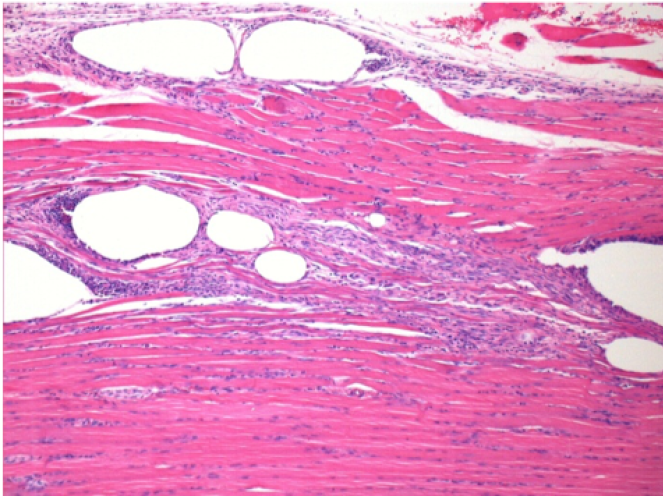

10 días después de la inyección de Endopeel 0,1 ml en el músculo pretibial derecho.

Aquí puede ver la formación de las vacuolas que están rodeadas de linfocitos. Las vacuolas son diferentes a la necrosis tisular. La presencia de linfocitos está relacionada con la permeabilidad de las membranas celulares.